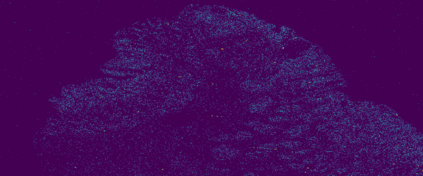

The usage of chemical imaging technologies is becoming a routine accompaniment to traditional methods in pathology. Significant technological advances have developed these next generation techniques to provide rich, spatially resolved, multidimensional chemical images. The rise of digital pathology has significantly enhanced the synergy of these imaging modalities with optical microscopy and immunohistochemistry, enhancing our understanding of the biological mechanisms and progression of diseases. Techniques such as imaging mass cytometry provide labelled multidimensional (multiplex) images of specific components used in conjunction with digital pathology techniques. These powerful techniques generate a wealth of high dimensional data that create significant challenges in data analysis. Unsupervised methods such as clustering are an attractive way to analyse these data, however, they require the selection of parameters such as the number of clusters. Here we propose a methodology to estimate the number of clusters in an automatic data-driven manner using a deep sparse autoencoder to embed the data into a lower dimensional space. We compute the density of regions in the embedded space, the majority of which are empty, enabling the high density regions to be detected as outliers and provide an estimate for the number of clusters. This framework provides a fully unsupervised and data-driven method to analyse multidimensional data. In this work we demonstrate our method using 45 multiplex imaging mass cytometry datasets. Moreover, our model is trained using only one of the datasets and the learned embedding is applied to the remaining 44 images providing an efficient process for data analysis. Finally, we demonstrate the high computational efficiency of our method which is two orders of magnitude faster than estimating via computing the sum squared distances as a function of cluster number.